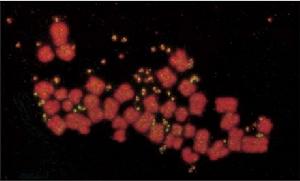

圖16-7Myc基因擴增形成雙微核(黃色)的核型在某些造血系統惡性腫瘤中,癌基因擴增是一個極常見的特徵,如前髓細胞性白血病細胞系和這類病人的白血病細胞中,c-myc擴增8~32倍。癌基因擴增的染色體結構有:①雙微體(doubleminutechromosomes,DMs),無著絲粒,成對分布於細胞中的微小染色體(圖16-7);②均染區(homogenouslystainedregion,HSR),是染色局部擴增形成的(圖16-8);③姊妹染色單體非均等交換(unequalsisterchromatidexchange,USCE),G2期由於姊妹染色單體之間發生了非均等交換,結果一個子細胞中該染色體較長,具有同源重複(基因擴增),另一個細